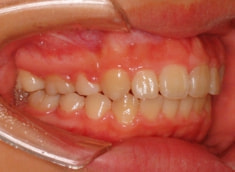

治療後(1年2ヶ月後)

治療開始から5ヶ月後